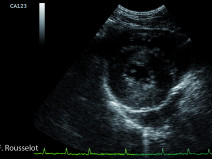

• L’examen échocardiographique

Être capable :

d’enregistrer en mode Doppler des flux transvalvulaires normaux ;

de réaliser une échographie thoracique non cardiaque.